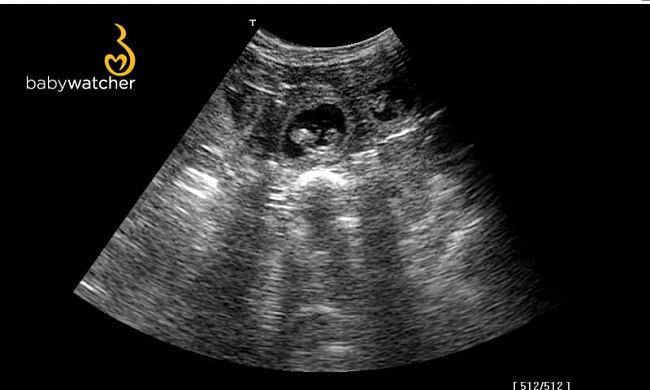

Hier noch einige Ultraschallbilder vom 22.02.2021 Es ist einiges los in Melodies Bauch und wir sind sehr gespannt was unsere Zaubermaus um den 27. März in die Wurfkiste legen wird. Jetzt heißt es erst mal unsere werdende Mama weiterhin ordentlich verwöhnen mit Streicheleinheiten, Bewegung und einigen Extraleckereien :-)

Dicht an dicht gekuschelt sitzen die J-chen gleichmäßig in den Gebärmutterhörnern verteilt.

24.02.2021 Ultraschall am 32. Tag der Trächtigkeit

Ein erneuter Ultraschall zuhause, ganz entspannt zeigte zahlreiche kleine Passagiere in Melodies Bauch, dicht an dicht gekuschelt <3